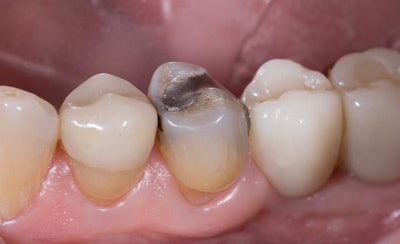

A 65-year-old healthy man presented for a hygiene visit and exam with a large, failing distal-occlusal amalgam on tooth #20, a mesial marginal ridge fracture, mesial recurrent decay, and buccal cuspal wear with cupping erosion (figure 1, below). An intraoral image illustrating the condition of the tooth was taken with Primescan (Dentsply Sirona) for patient education. The clinical image was shown to the patient and, upon being advised of the findings, he agreed to proceed with a CEREC (Dentsply Sirona) single-visit, full-contour crown restoration.